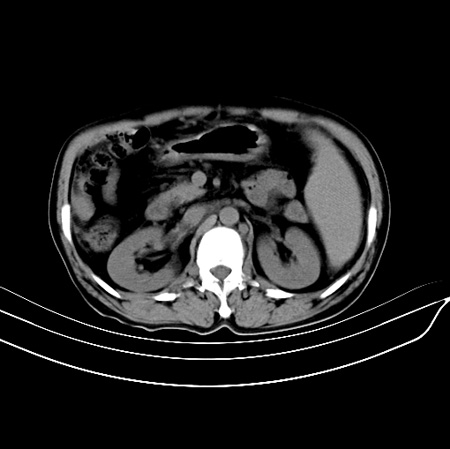

以下是引用江尾海头在2007-9-7 19:01:00的发言:[br]肝叶比例失调,肝边缘高低不平,尾状叶增大,肝裂增宽。肝右叶见较大密度减低影,边缘欠清。脾脏明显增大,胃底及奇静脉半奇静脉曲张。胆囊未见明显显示。 考虑:1、肝癌。2、肝硬化伴脾大静脉曲张。

以下是引用zhangxu5888在2007-9-7 22:31:00的发言:[br]1、肝硬化,食管 胃底及奇静脉半奇静脉曲张;2、脾脏肿大; 3、肝右叶的病灶呈锲性改变,内可见条片状钙化,边界清晰,密度明显低于周围正常肝组织,我觉得肝癌可能性不是很大, 同意楼上观点,有可能是栓塞,建议增强.